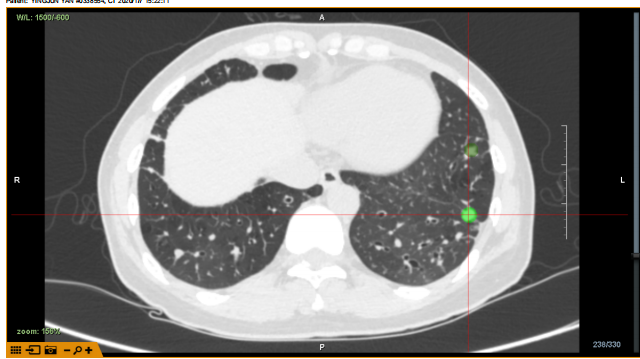

揭牌仪式后,在龙发主任开展手术演示。手术前,龙发主任与多位印度专家针对手术病例进行了谈论,制定了手术路径,其中包括一台气道内活检病例(Lungpoint),以及两台无明显气道相通病例(BTPNA)。隧道路径分别为36mm及34mm。均成功建立隧道,X光及超声小探头确认抵达病灶,耗时分别为20分钟、15分钟。

病例2:病灶位于LB9,大小约9mm,隧道路径约34mm,POE 点位于RB9亚亚段。

病例2

X光与超声确认抵达病灶